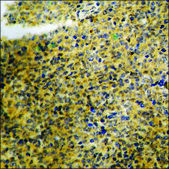

ELISA: 1:1000, immunohistochemistry: 1:50-1:100

phosphorylation (pTyr1048)

The antiserum was produced against synthesized peptide derived from human VEGFR1 around the phosphorylation site of Tyr1048.

Immunogen Range: 1016-1065